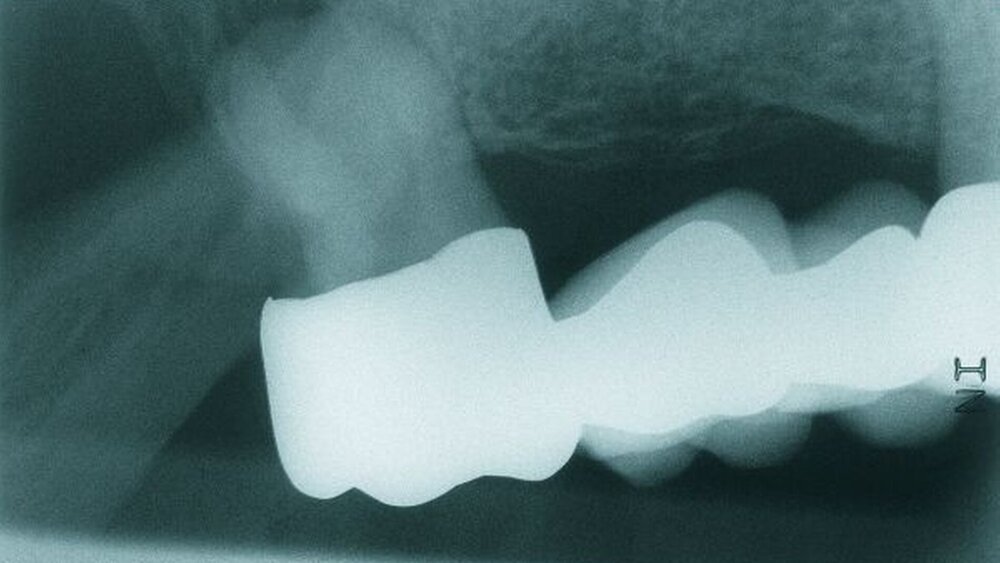

Auf dem vor Anfertigung des Zahnersatzes angefertigten OPG sowie den angefertigten Zahnfilmen der regiones 17 und 27 waren generalisierte horizontale Knochenverluste im Bereich aller verbliebenen Zähne erkennbar. Die Zähne 17 und 27 wiesen zudem vertikale Knocheneinbrüche auf. Eine radiologische Furkationsbeteiligung ließ sich in beiden Fällen nachweisen. Der Zahn 47 war wurzelkanalgefüllt.

Obwohl der Zahn 47 eine radiologisch nicht vollständig bis zum radiologischen Apex reichende Wurzelfüllung aufwies, wurde auf eine Revision der Wurzelfüllung aufgrund einer seit mehr als 15 Jahren bestehenden Beschwerdefreiheit des Patienten und vollständiger Symptomlosigkeit des Zahnes verzichtet [Peak et al., 1994]. Der Patient wurde über diese Sachverhalte ausführlich aufgeklärt und erklärte sich mit dem Belassen der Wurzelfüllung einverstanden.